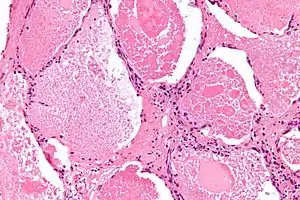

| Micrograph of pulmonary alveolar proteinosis, showing the characteristic airspace filling with focally dense globs referred to as chatter or dense bodies. H&E stain. | |

Lung washings or tissue for histopathologic analysis are most commonly obtained using bronchoalveolar lavage and/or lung biopsy.[12] Characteristic biopsy findings show filling of the alveoli (and sometimes terminal bronchioles) with an amorphous eosinophilic material, which stains strongly positive on PAS stain and the PAS diastase stain. The surrounding alveoli and pulmonary interstitium remain relatively normal.[13] Electron microscopy of the sample, although not typically performed due to impracticality, shows lamellated bodies representing surfactant.[14] An alternative diagnosis with similar histomorphologic findings is Pneumocystis jirovicii pneumonia.[14]

Lung washings characteristically yield a fluid which is "milky"composition. Under the microscope, samples show 20-50 micrometer PAS-positive globules on a background of finely granular or amorphous PAS-positive material. There is typically a low numbers of macrophages and inflammatory cells (although this is variable).[13][14]